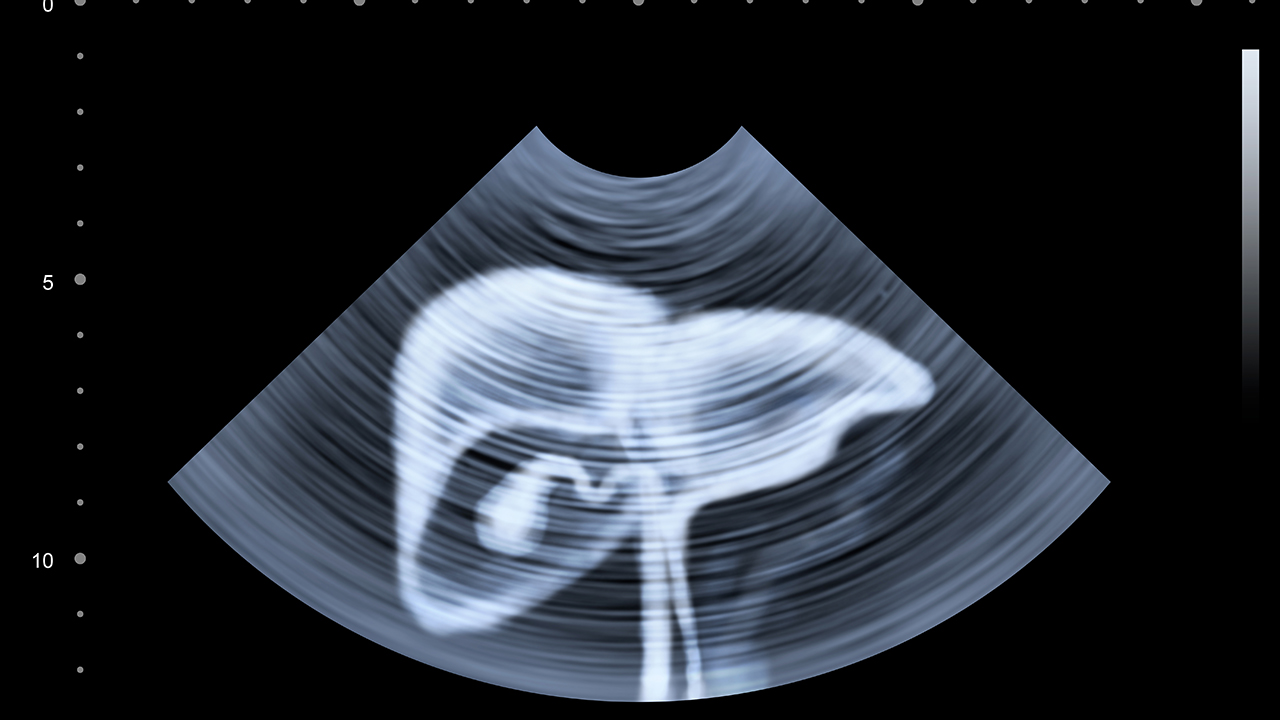

3、其他方式:对于晚期肝癌患者来说,由于肿瘤体积较大,压迫周围组织可能会引起疼痛。此时可以考虑介入治疗或者放疗、化疗等方式控制病情进展,减轻疼痛症状。